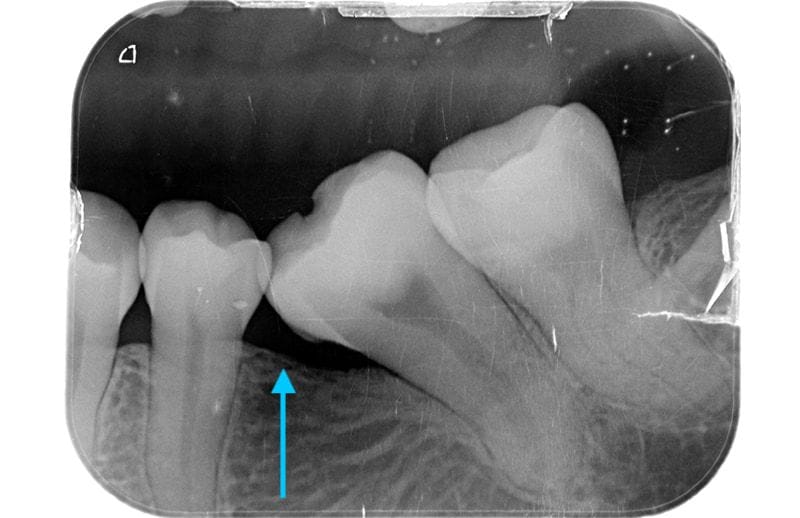

左下區域很早第一大臼齒就缺牙。因為缺牙不補,久了以後齒列空間改變,後面兩顆臼齒往前傾倒,造成吃東西時食物堆積難以清潔的問題。左邊上面後方假牙,時間久遠,密合度已經不佳,這會是清潔的死角,因而造成牙菌斑堆積導致牙齦發炎流血。

圖示:長期缺牙不補導致鄰牙移位與空間喪失,影響咬合更產生食物塞牙縫與牙周問題